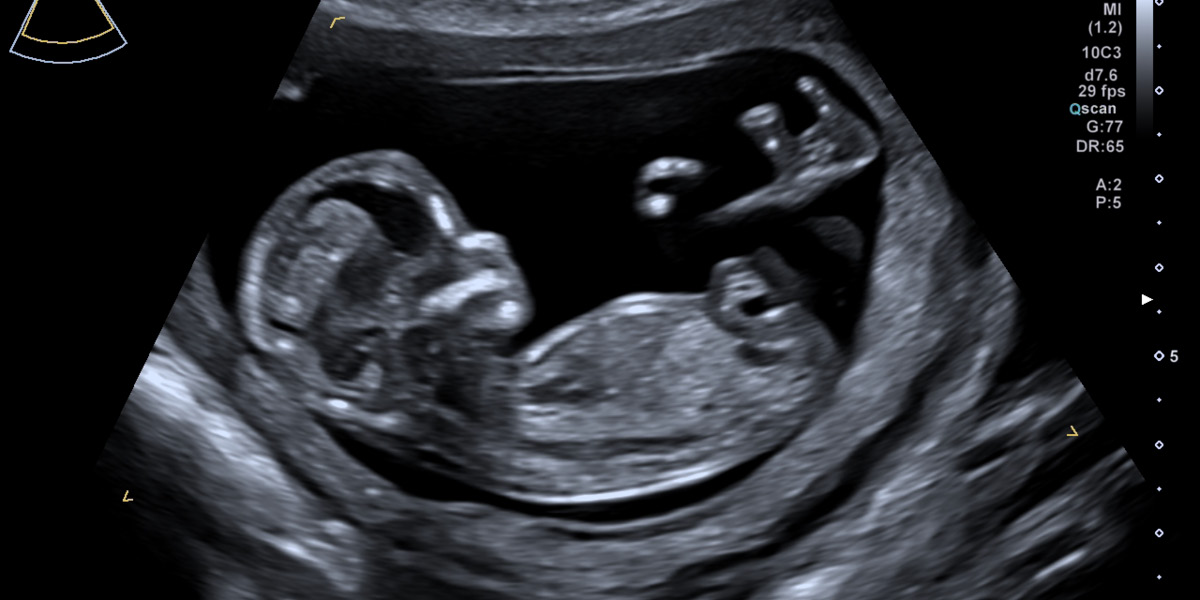

Das Baby in der Übersicht. So können Wachstum und Proportionen, Herzschlag und Gesicht gesehen werden.

Auch Arme und Beine mit Händen und Füßen lassen sich bereits untersuchen.